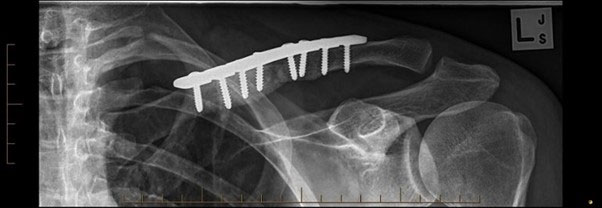

We organised some new x-rays, which revealed the difficult problem we had. I believe that his fracture had healed in a malunited position despite the original plate and that over time and with his various activities he had managed to bend the plate.

The lump from the bent plate was obvious as was the shortening of the clavicle leading to poor posture.

We discussed the options of treatment and he was keen for me to remove the bent plate, re-fracture his clavicle and then bring it out to length before applying another plate. The operation took about an hour and a half but I think the results speak for themselves (see below).